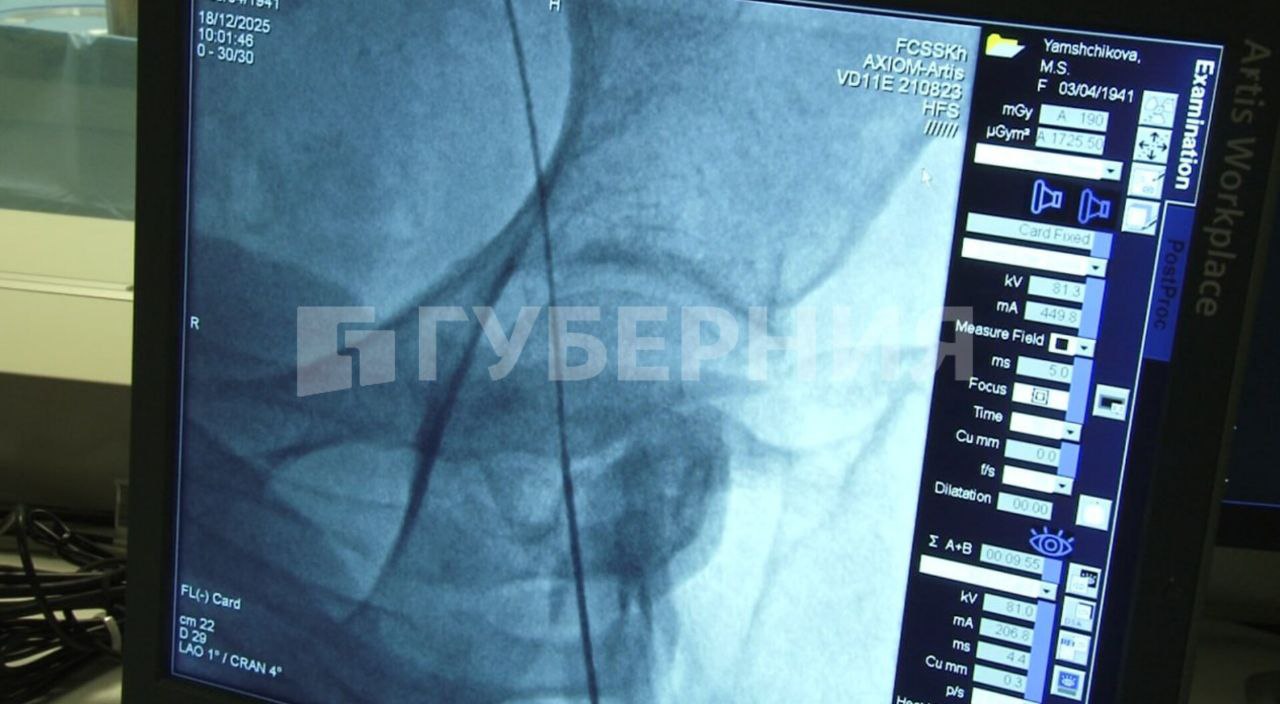

Во время операции хирурги вводят катетер, который содержит в себе две «ловушки». Они позволяют частично перекрывать кровоток по артериям мозга. Таким образом, объясняют специалисты, операция становится более безопасной.

«То есть фильтруется та часть, которая потенциально может вызывать инсульты и слабоумие – так называемую деменцию. Это мелкие частицы, которые ловушка позволяет задержать во время операции, не давая проникнуть в головной мозг и нарушить его питание», – рассказал заведующий отделением рентген-хирургии федерального центра сердечно-сосудистой хирургии Хабаровска Константин Поляков.